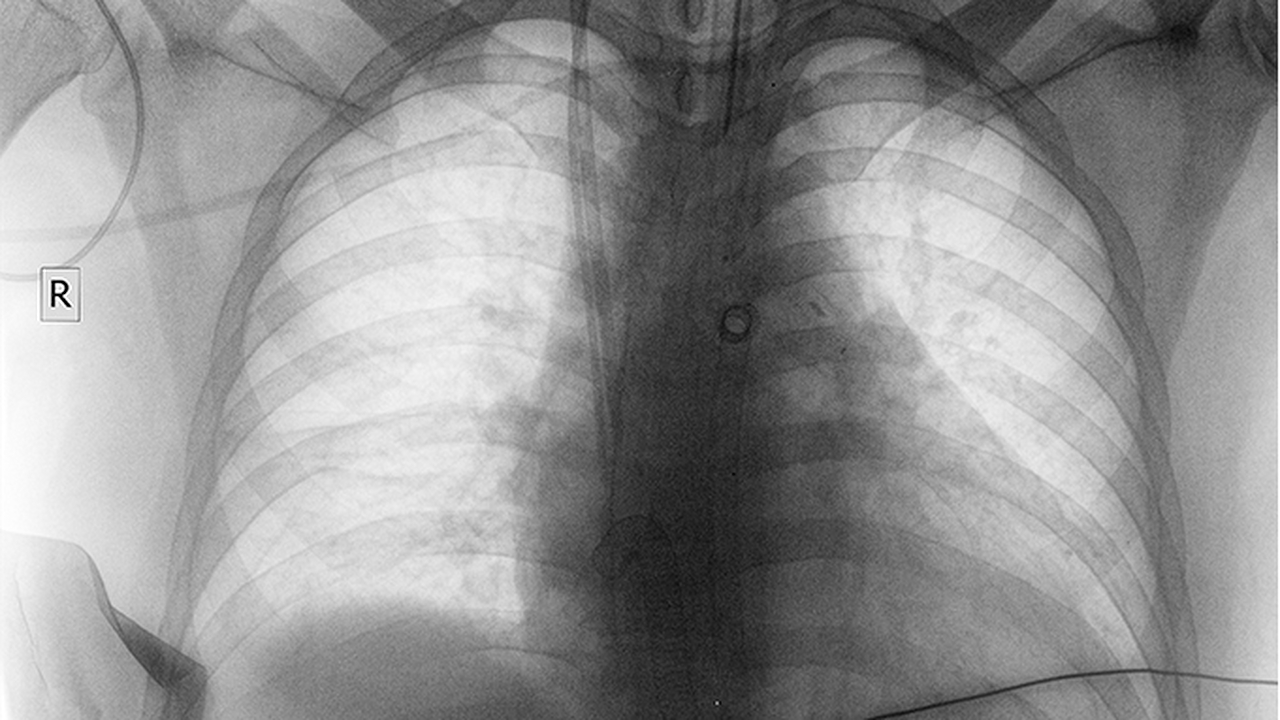

肺癌的发病原因复杂,与吸烟、环境污染、职业暴露、遗传因素等密切相关。早期诊断和规范治疗对提高生存率至关重要。

广州医科大学附属第一医院呼吸内科在肺癌早期诊断和介入治疗方面具有特色。医院开展支气管镜、EBUS等检查技术,能够早期发现肺部病变。在肺癌综合治疗方面,医院注重多学科协作,为患者制定优治疗方案。